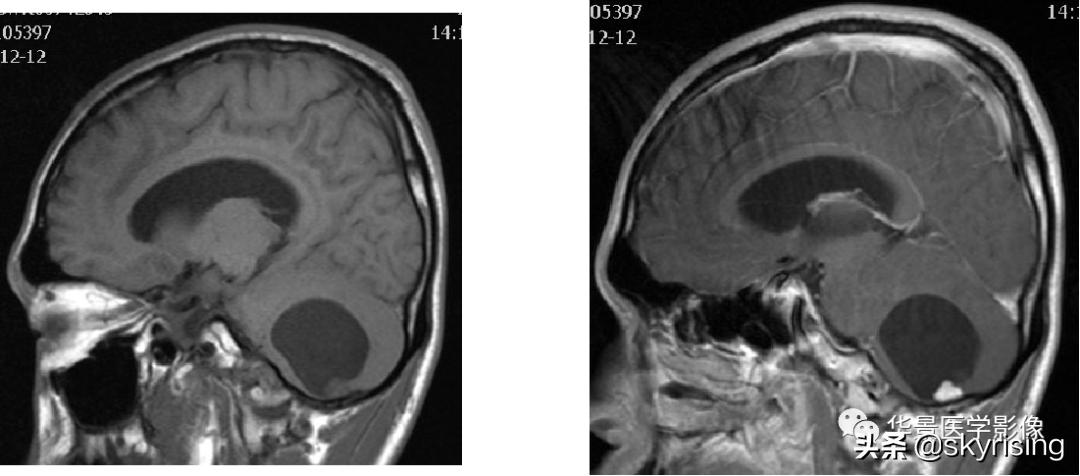

以下依次为T2WI、FLAIR、T1WI、增强、DWI及ADC:

上图白色箭头:小脑延髓池内延髓背侧不规则形团块影,延髓受压变形。

黄色箭头:走行与病灶边缘的流空信号血管影。

上图白色箭头:小脑延髓池内延髓背侧不规则形团块影,小脑半球、延髓、第四脑室受压变形,所见诸脑室未见增宽。

蓝色箭头:延髓受压前后径变窄,T1信号减低,考虑合并水肿。

黄色箭头:病灶边缘见流空信号血管影。

小脑延髓池内见不规则异常信号影,呈长T1长T2信号,内部信号不均,边缘见稍粗大流空信号血管影,FLAIR少许片状低信号,增强呈明显强化,DWI不均质低信号,ADC不均质高信号。小脑半球、延髓、第四脑室受压变形。临近延髓变窄,呈长T1长T2信号。

总体以不规则实性占位病变,临近走行血管流空信号影,增强明显强化,DWI低信号为特点。